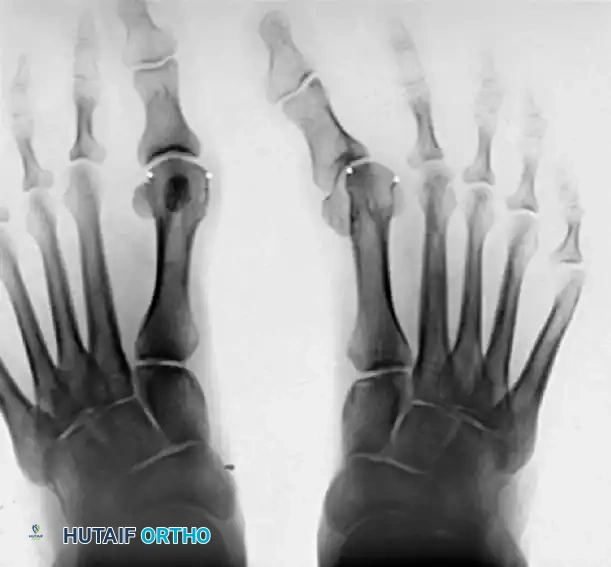

- Consolidation Phase: Once the desired length is achieved, distraction is halted. When radiographic evidence of consolidation (corticalization of the regenerate) is observed, partial weight bearing is permitted. The external fixator remains in place until full, robust consolidation is visible on multiple radiographic views. Following fixator removal, the patient may transition to full weight bearing and normal shoe wear as tolerated.

Figure 81-77: (A) Fixed hallux varus after a McBride bunionectomy. (B) Hallux varus after a McBride bunionectomy with fibular sesamoid excision. Removing the fibular sesamoid eliminates the valgus-producing moments of the adductor hallucis and the lateral head of the flexor hallucis brevis.

Figure 81-76: (A) Relatively mild hallux varus with symptomatic degenerative arthritis of the first metatarsophalangeal joint. (B and C) Arthrodesis was chosen as the definitive treatment due to the presence of advanced degenerative joint disease.